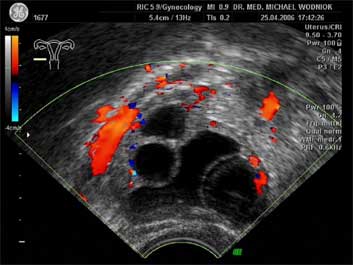

Ultraschall des kleinen Beckens mit der Vaginalsonde Die Ultraschalluntersuchung ist ein bildgebendes Verfahren, welches die Reflektion oder Echos von Ultraschallwellen in den unterschiedlichen Geweben und Organen ausnützt um computergestützt Schnittbilder aus dem Inneren des Körpers zu erstellen. Durch moderne hochleistungsfähige Mikroprozessoren ist es in den letzten Jahren möglich geworden, auch 3-dimensionale oder sogar bewegte 3-dimensionale (4-D) Bilder bzw. Bildsequenzen zu erzeugen. Beides können wir Ihnen in der Praxis anbieten. Eine Ultraschalluntersuchung ist ungefährlich und schmerzfrei. Durch die Anwendung von Dopplerverfahren, mit welchen wir den Blutfluss in den Organen feststellen und messen können, erweitern wir die Untersuchung um die funktionelle Dimension. Ein weiterer Bestandteil unseres Leistungsspektrums ist die farbkodierte Dopplersonographie. Farbkodiert sind entweder die Richtung des Blutflusses oder dessen Intensität. Über die computergestütze Berechnung des Blutflusswiderstandes ist im Einzelnen eine Aussage bzw. Vorhersage über die qualitative und quantitative Durchblutung möglich. (Plazentadurchblutung, kindliche Blutgefässe, Durchblutungsmuster bei verschiedenen Tumoren des Unterleibes und der Brustdrüsen) Ultraschalluntersuchungen haben in unserem Fachgebiet vielfältige Anwendungsmöglichkeiten gefunden. Besonders faszinierend ist der Einsatz im Bereich der vorgeburtlichen Diagnostik. Bereits in der 10. Schwangerschaftswoche ist es möglich, die Extremitäten des Embryos darzustellen und Aussagen zum Körperumrissbild zu machen (Ausschluss von Spaltbildungen, Nackentransparenzmessung). Auch im Bereich der Gynäkologie ist die Bedeutung des Ultraschalls stetig gewachsen und hat sich als erweiterte Vorsorge etabliert. Durch die vaginale Ultraschalluntersuchung können bereits kleine Veränderungen entdeckt werden, die sich der manuellen Tastuntersuchung noch entziehen. Auffällige Tastbefunde an den Eierstöcken sind durch den Einsatz von 3D / 4D in Kombination mit der Farbdoppleruntersuchung besser interpretierbar und können dadurch Frauen unnötige abklärende Operation ersparen. Die Anwendung des 3D Ultraschall, insbesondere im Coronarschnitt, lässt eine effektive Beurteilung für Veränderungen (Polypen, Karzinome) der Gebärmutterschleimhaut zu. ![]() ![]() ![]() ![]()